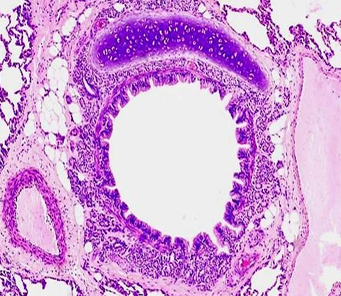

Section in the lung showing intrapulmonary bronchus

Bronchus

Intra pulmonary bronchus

1- epithelium, 2- smooth muscle, 3- cartilage